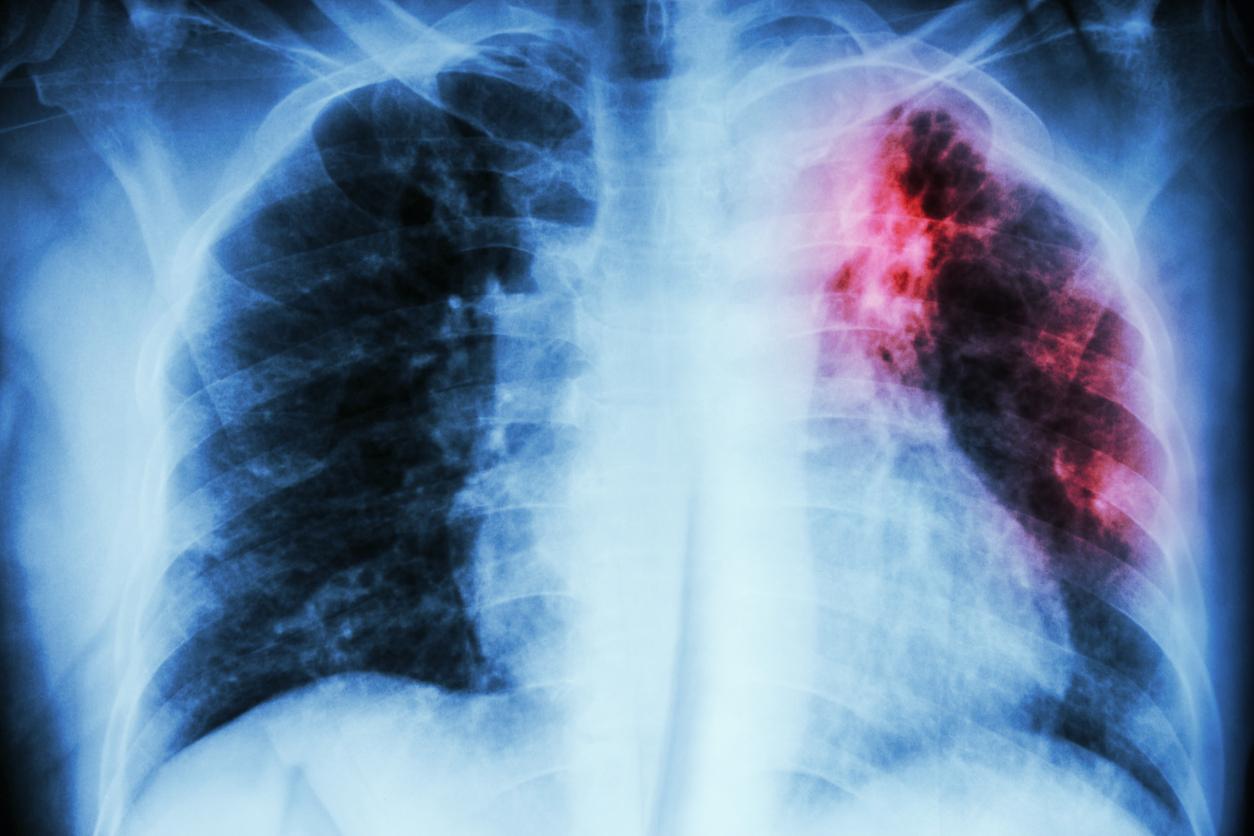

Le diagnostic de la tuberculose est assuré par des examens qui mettent en évidence le germe responsable sur des prélèvements (par examen microscopique, culture ou test d’amplification génique). D’autres examens comme les radios et scanners recherchent les lésions entraînées par la maladie. Comme il existe de nombreuses localisations possibles, d’autres tests d’imagerie ou de biopsie sont parfois nécessaires.

Le dépistage chez des personnes qui n’ont pas de symptôme ou ne s’en sont pas rendu compte, repose sur certains tests et examens : examen clinique, radio pulmonaire, examen bactériologique des expectorations (crachats) et/ou tests d’amplification génique.